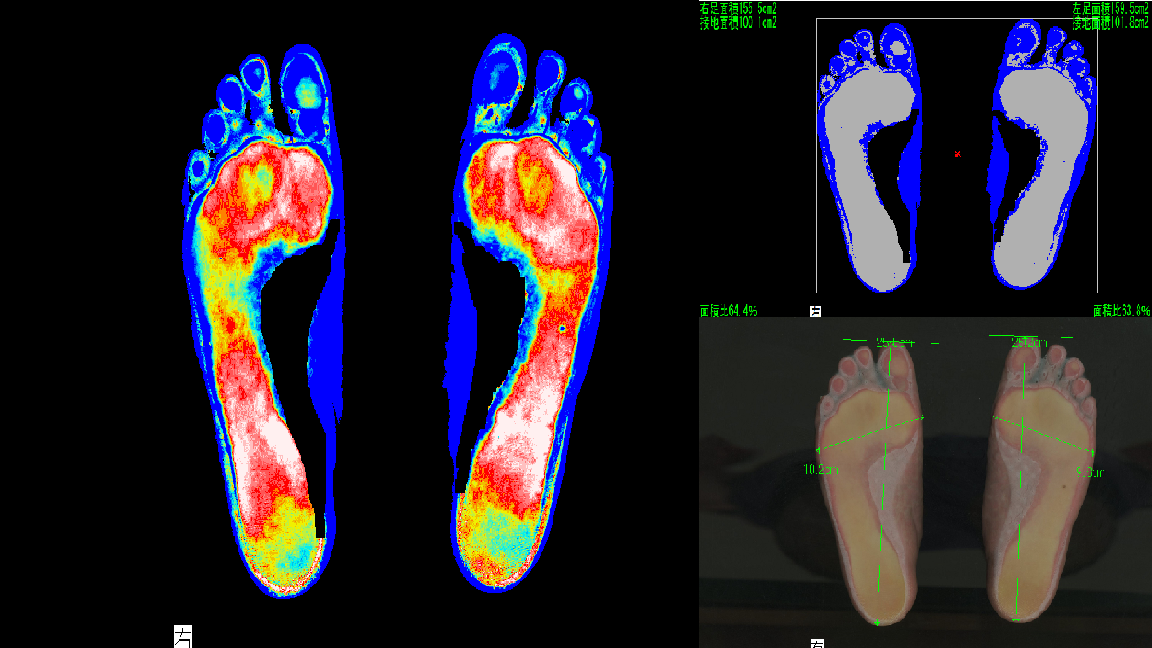

【特徴1】機器による徹底分析

テレビでも紹介された足の分析装置で、重心・浮き指・足圧を正確に計測。あなただけの痛みの原因をデータで明らかにします。